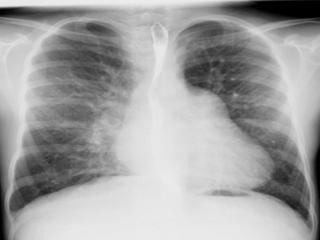

3. Rx. poate arata:

o silueta cardiaca mitrala,

largirea AS (PA, OAS, LS),

dublu contur dr.,

calcificari mitrale sau de AS,

VS mare sau mic,

semne de hipertensiune veno-capilara:

redistributie venoasa lobara sup,

edem interstitial,

linii Kerley exprima staza limfatica (A-la hil, B-la baza SM stransa, C-intre),

edem alveolar,

epansament pleural.

hemosideroza,

calcificari

pulmonare,

infarct pulmonar,

alte boli pulmonare

asociate.